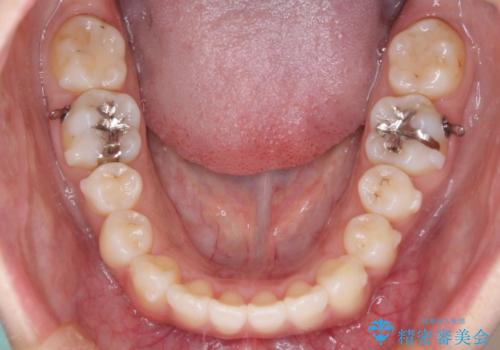

- 前歯の歯並びの改善を希望され来院された患者様です。

初診時の歯並びの状態としては、上下ともに全体に及ぶの中等度のがたつき(叢生)があり、全特に左上の前歯は1本だけ引っ込んでいる状態でした。

抜歯は行わず上顎の奥のスペースを利用して歯をスライドする方法の他に歯列弓の拡大やディスキング(歯と歯の間の隙間を作る処置)を行い叢生を改善しました。

歯の大きさの不揃いが原因の正中のズレは、ディスキング量を調整することで合わせました。

見た目、嚙み合わせ及び、治療期間や施術内容に大変ご満足いただきました。